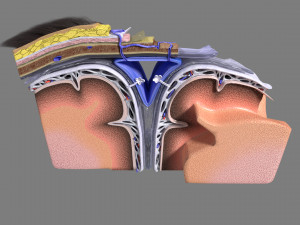

A blend model of brain along with its covering layers (meninges), skull bone and scalp labelled in detail and anatomically precise. The parts depicted are white, gray, pia, arachnoid, dura, bone, skin, fat, aponeurosis, periosteum, falx cerebri and more.

The material is high resolution image textures and normal maps based on non overlapping UVs. The texture and normal maps are packed with the blend file itself.